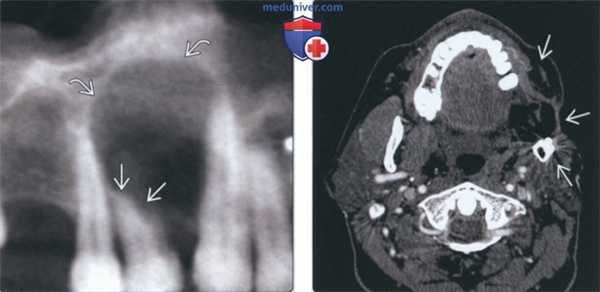

(Слева) На панорамной реформатированной КЛКТ у этого же пациента определяется резорбция корня зуба наряду с хорошо отграниченным рентгенонегативным образованием.

(Справа) На аксиальной КТ с КУ определяется деформация левой половины лица в результате предыдущей резекции амелобластомы, метастазирующей в мягкие ткани шеи и шейные позвонки. Злокачественная амелобластома в этом примере гистологически выглядит доброкачественной (отличной от амелобластического рака), но метастазирует в лимфоузлы и в отдаленные органы.